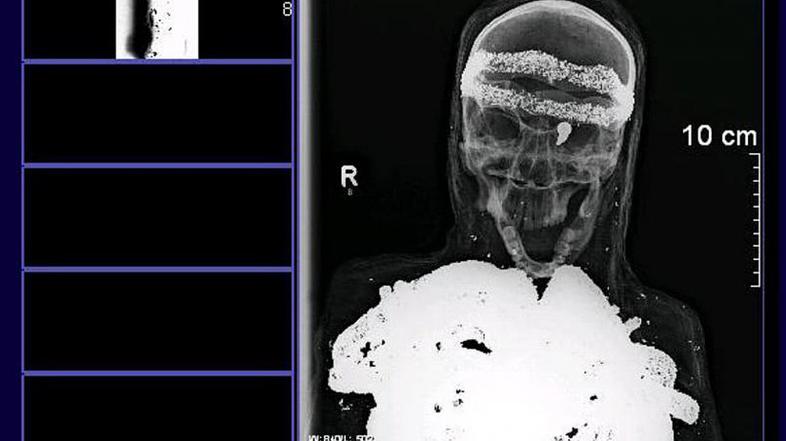

Magnetna resonanca je pokazal, da je človeška lobanja relativno dobro ohranjena, iz leve očesne jamice pa štrli puščica. Uganko še povečuje posmrtna maska in to, da  je rentgen pokazal kovinske plasti, ki prekrivajo kosti 1,49 metra dolgega bitja. Spola niso mogli potrditi. "Porajajo se le nova in nova vprašanja," je dejal Lutz-Wolfgang Kettler, oče dečka, ki je našel sarkofag. K temu prispeva tudi dejstvo, da so povoji novejšega datuma – izdelani so bili strojno v 20. stoletju, poroča AFP.